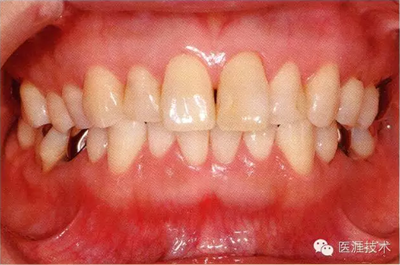

28歲女性的健康口腔內(nèi)部

圖為28歲女性,無特殊全身疾病,不抽煙。10年前來院就診保養(yǎng)3年,期間中斷過,現(xiàn)又開始。齲壞風(fēng)險(xiǎn)高,當(dāng)初初診時(shí)已有好幾顆牙的鄰面有填充物,再填充了3牙的鄰面齲,現(xiàn)牙周組織健康。